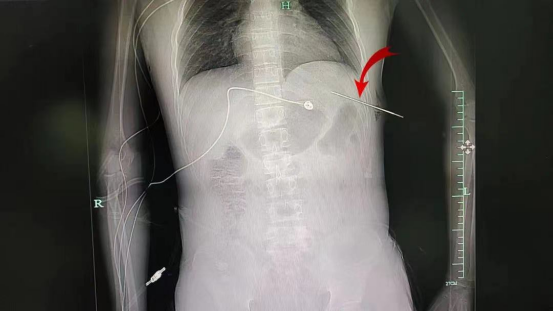

CT可见水果刀在位

患者送至手术室后,术中探查发现患者存在创伤性肝破裂、腹腔积液、肺破裂、膈肌破裂、血气胸,属于胸腹联合伤(胸腹联合伤伤情严重而复杂,危险性较大,其休克发生率高达60%,死亡率高达25%~35%),团队医生即行胸腔镜探查+膈肌修补,手术过程顺利,术后患者转ICU。